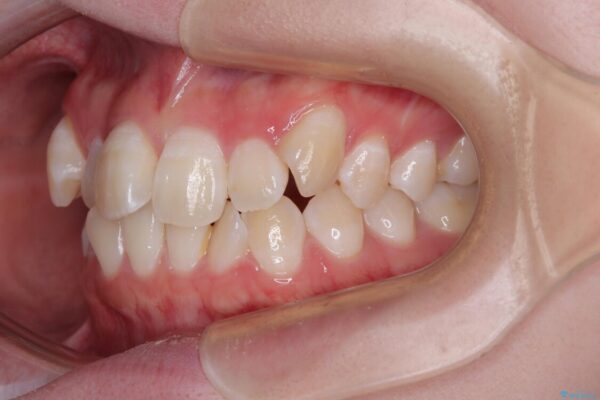

上下の正中(真ん中のライン)もずれることなく、バランスの取れた美しい歯並びに。笑顔に自信を持てる仕上がりとなりました。

「もっと時間がかかると思っていましたが、あっという間でした。装置も思ったより気にならず、前歯がきれいに並んでとても満足しています。」とうれしいお言葉をいただきました。

治療後

• 【モニター】前歯のデコボコをスッキリ解消!目立ちにくいワイヤー矯正でスピーディに治療完了 治療後画像